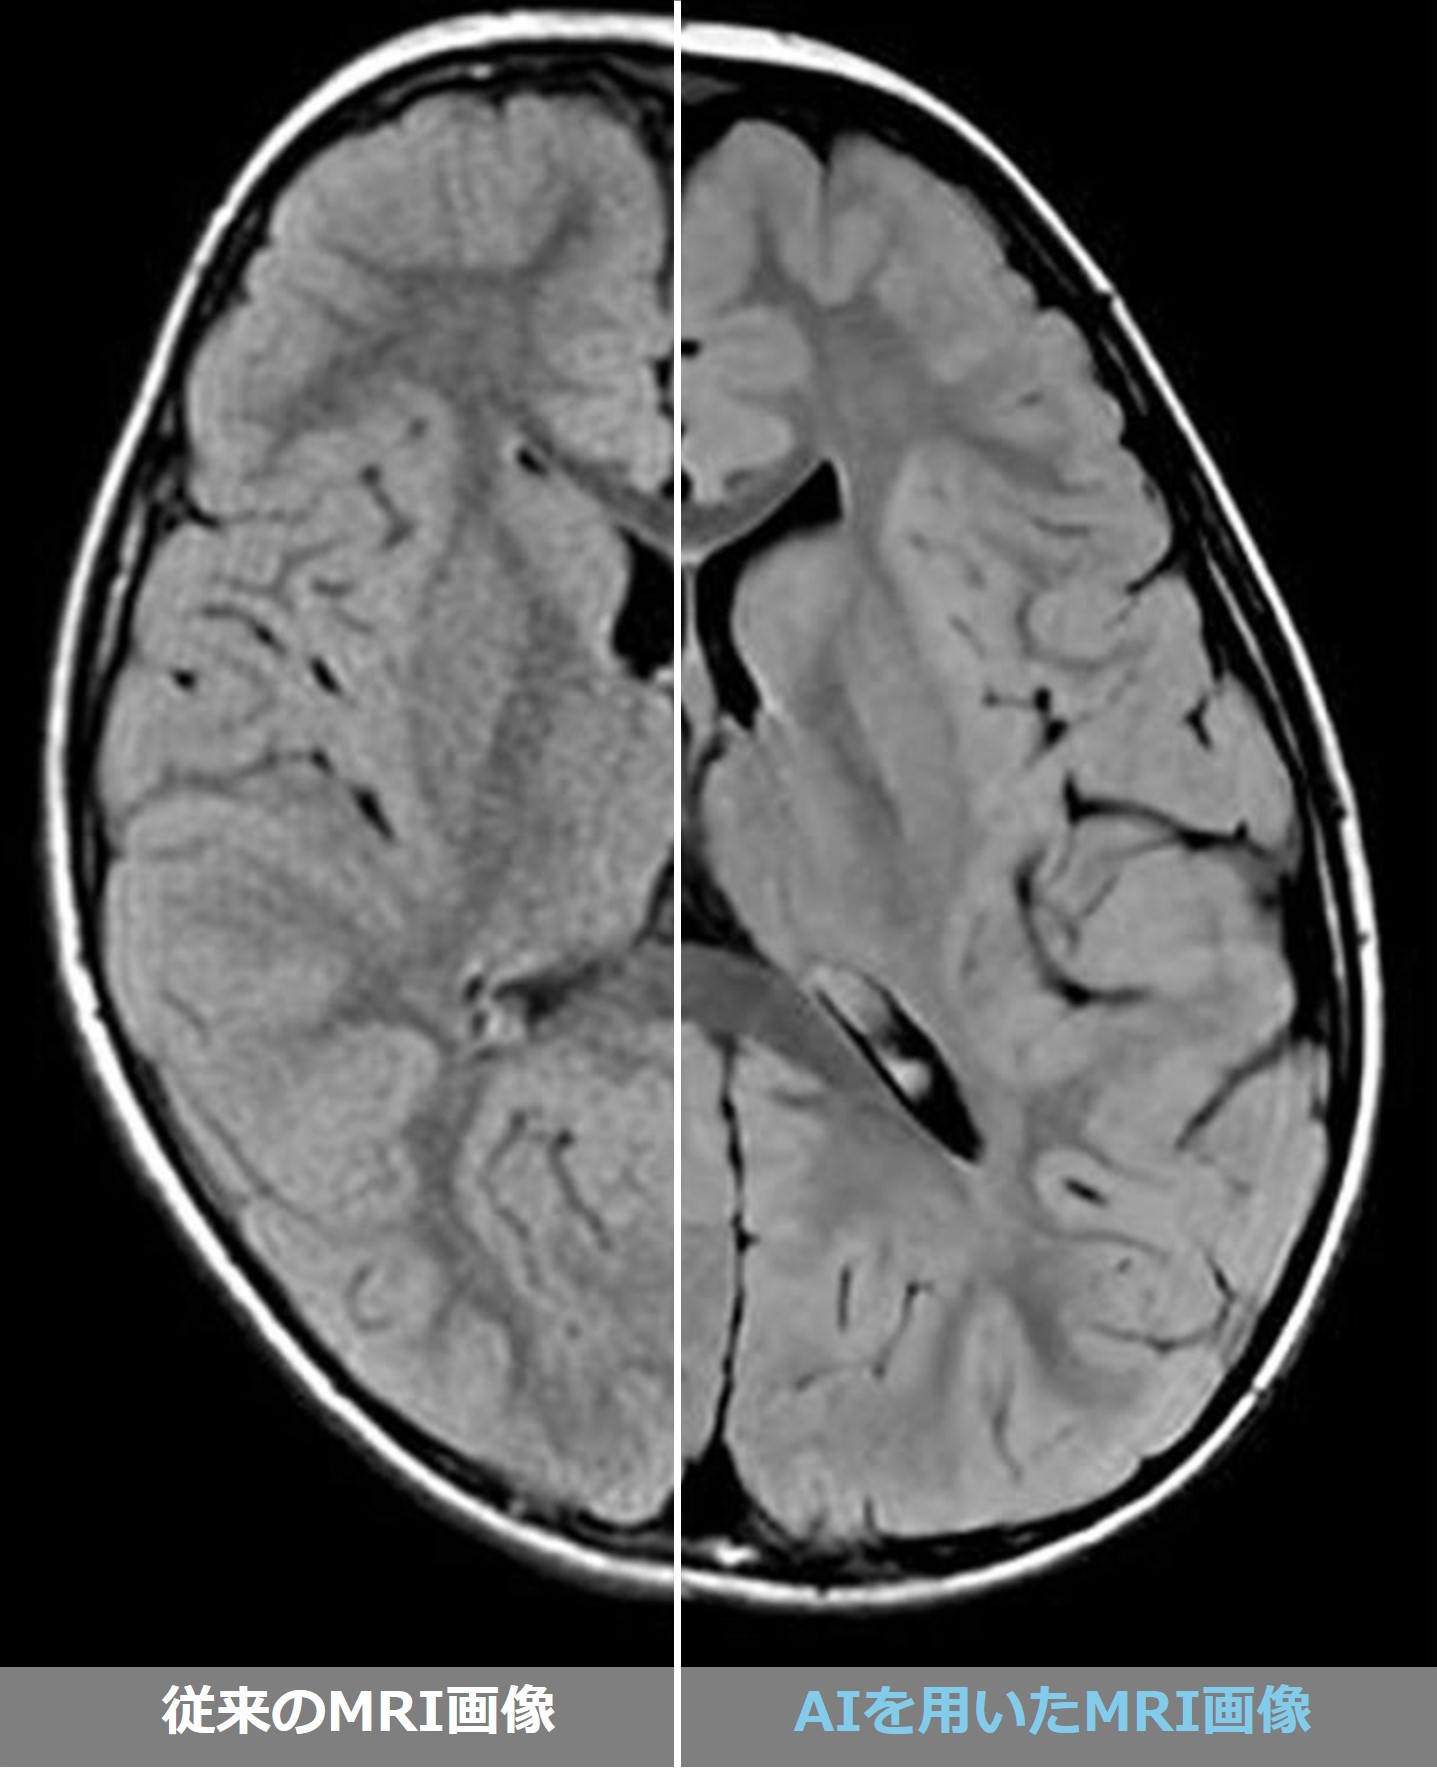

2024年9月、当院のMRIに革新的なAI機能を用いた

アプリケーションを導入しました。

従来のMRI画像と比較して、大幅な画質の向上が

期待できます。

さらに、撮像時間の短縮にも効果を発揮します。